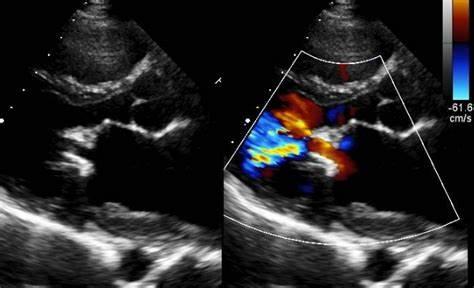

At Evergreen Health Centre, we conduct the best echo colour Doppler in Konnagar, Liluah, and Chandannagar. It helps in imaging the blood vessels which assists in indicating the speed and direction of the blood flow in the blood vessel. This kind of ultrasound technique is highly reliable in examining the heart function, checking the blood flow blockage, inspecting the damage to the blood vessels, examining the narrowing of the blood vessels, etc. We have a team of specialized doctors who perform the test very precisely and accurately.

• The Doctors tend to use the echo colour Doppler for accessing the functioning of the heart.

• It also helps in demonstrating the disease of the heart muscle, valves, and pericardium.